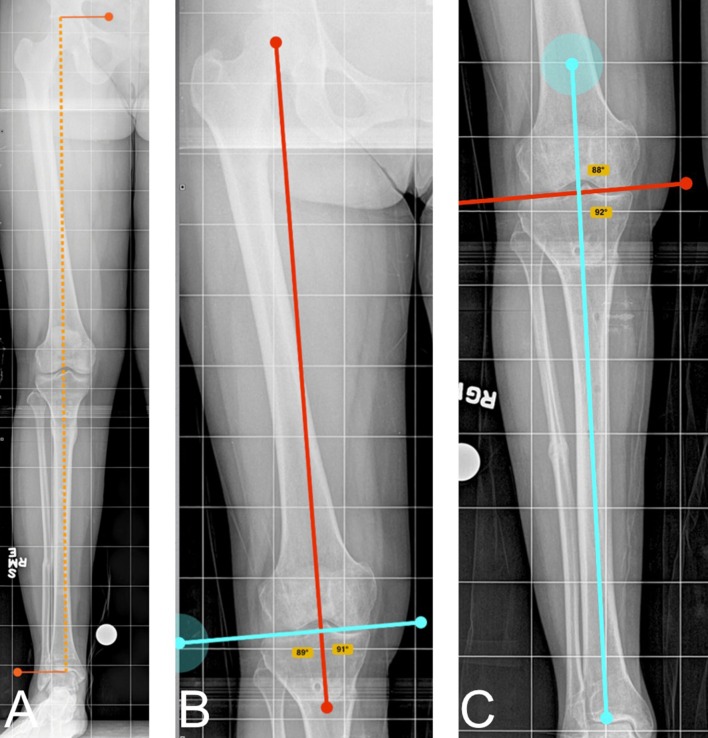

Four raters, an attending orthopaedic surgeon, a senior orthopaedic resident, a junior orthopaedic resident, and an orthopaedic physician assistant, measured each PACS and Bone Ninja image on four separate occasions with a minimum of 1 week between measurements and alternating PACS and Bone Ninja. They were timed during their last session with Bone Ninja and PACS. Satisfaction was determined by the question of which they would prefer using for deformity measurements. No participant had any financial or developmental involvement in the Bone Ninja app. The PACS measurements (Philips iSite Enterprise PACS, MA, USA) were completed on a 10.5 × 13 inch monitor. The iPad was an iPad 4th generation with 9.7-inch retina display. The four raters were allowed to keep the iPad at the end of the study. The measurements recorded for each image were the right and left total limb length (LL), lateral distal femoral angle (LDFA), and medial proximal tibial angle (MPTA) after calibration of each image using a 2.54-cm calibration ball (Fig. 1). Each participant was given instructions both verbally and on paper, and a hands-on demonstration on how to do the measurements on both Bone Ninja and PACS. The LDFA was measured as the lateral angle between the mechanical axis of the femur, from the center of the femoral head to the center of the knee, and the distal femoral joint line. The MPTA was measured as the medial angle between the mechanical axis of the tibia, from the center of the knee to the center of the tibial plafond, and the proximal tibial joint line.

Fig. 1.

Radiographic measurements as demonstrated on Bone Ninja. a Total limb length. b Lateral distal femoral angle (LDFA). c Medial proximal tibial angle (MTPA)

The intra-observer correlation coefficients were similar and highly correlated for LLD, LDFA and MPTA (Table 1). The limb length kappa value was 0.96 on the PACS and 0.95 on Bone Ninja, signifying an excellent agreement within the four subjects using both methods of limb deformity measurement (Fig. 1a). The LDFA kappa coefficient was 0.93 on PACS and 0.89 on Bone Ninja, signifying an excellent agreement when measuring LDFA within the four subjects (Fig. 1b). The MPTA kappa coefficient had a high correlation of 0.95 on PACS and 0.96 on Bone Ninja, demonstrating agreement between PACS and Bone Ninja for proximal tibial angle measurements (Fig. 1c). All intra-observer correlations were excellent; therefore Bone Ninja limb deformity measurements taken by one observer are as accurate as the measurements on PACS.